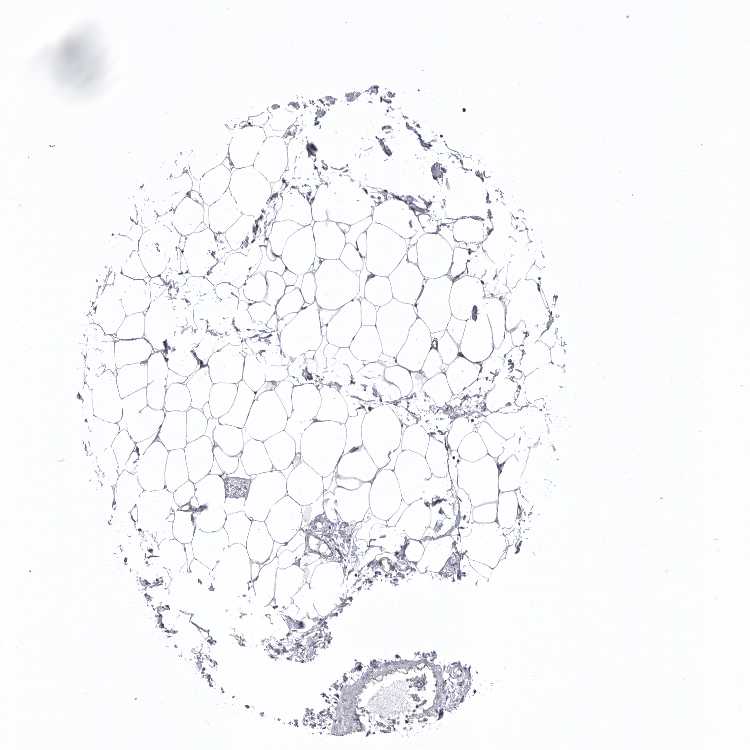

SOFT TISSUE 1 - Antibody stainingi

Antibody staining in the annotated cell types in the current human tissue is reported as not detected, low, medium, or high, based on conventional immunohistochemistry profiling in selected tissues. This score is based on the combination of the staining intensity and fraction of stained cells.

Each image is clickable and will lead to virtual microscopy that enables deeper exploration of all samples and also displays staining intensity scores, fraction scores and subcellular localization as well as patient and tissue information for each sample.

Antibody CAB025366

Fibroblasts Not detected

Peripheral nerve Not detected